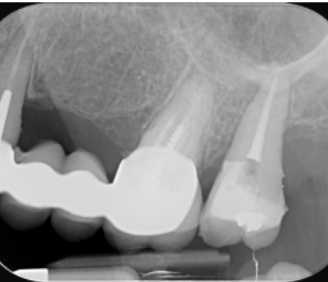

Endodontiste

Endodontie